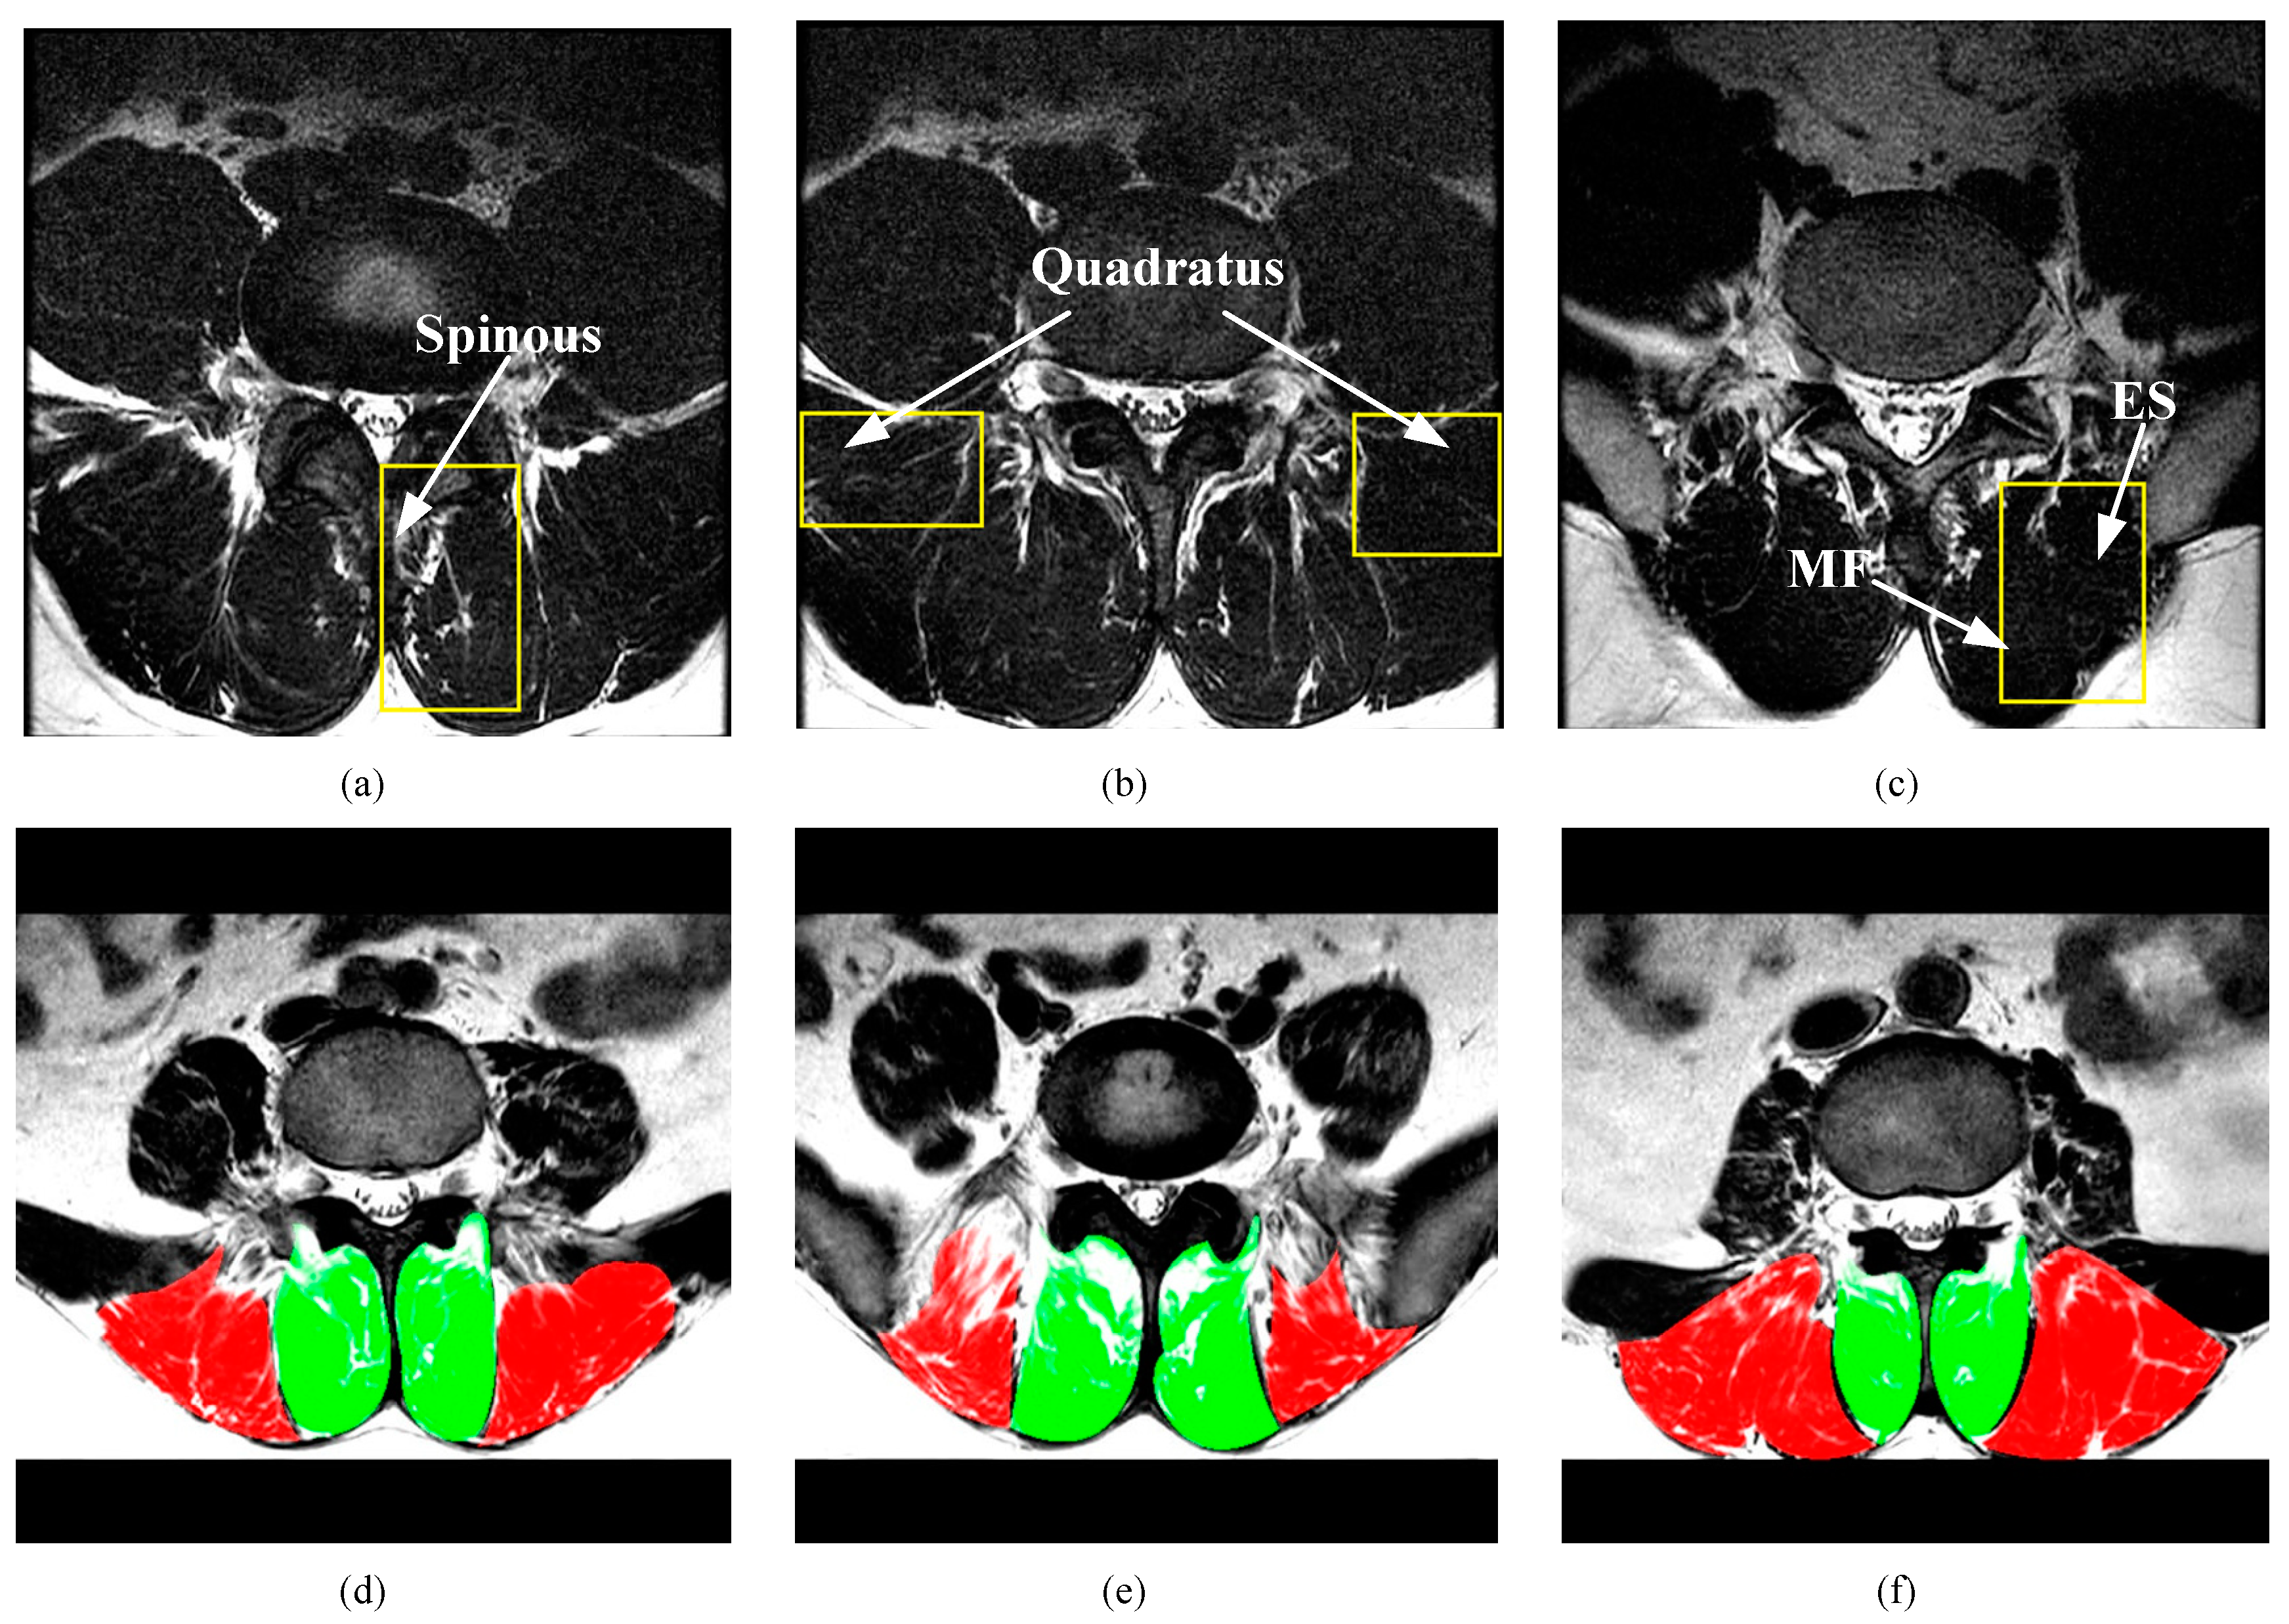

3.1. Dataset

3.4. Modules Analysis by Intra-Comparison

3.5. Comparison with other State-of-the-Art Methods